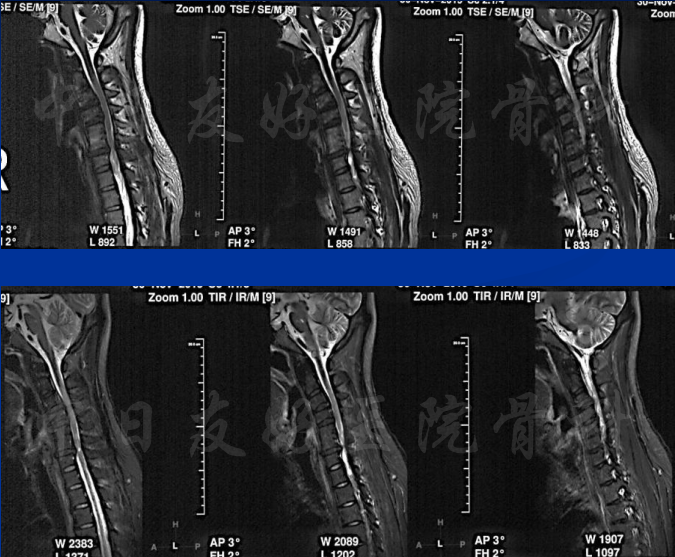

颈椎MRI

颈椎MRI

颈椎各节段MRI(上下滑动)

2019年11月30日 颈椎MRI提示:颈3/4颈4/5颈6/7椎间盘突出,椎管狭窄;颈5-6水平脊髓异常信号,变性可能。